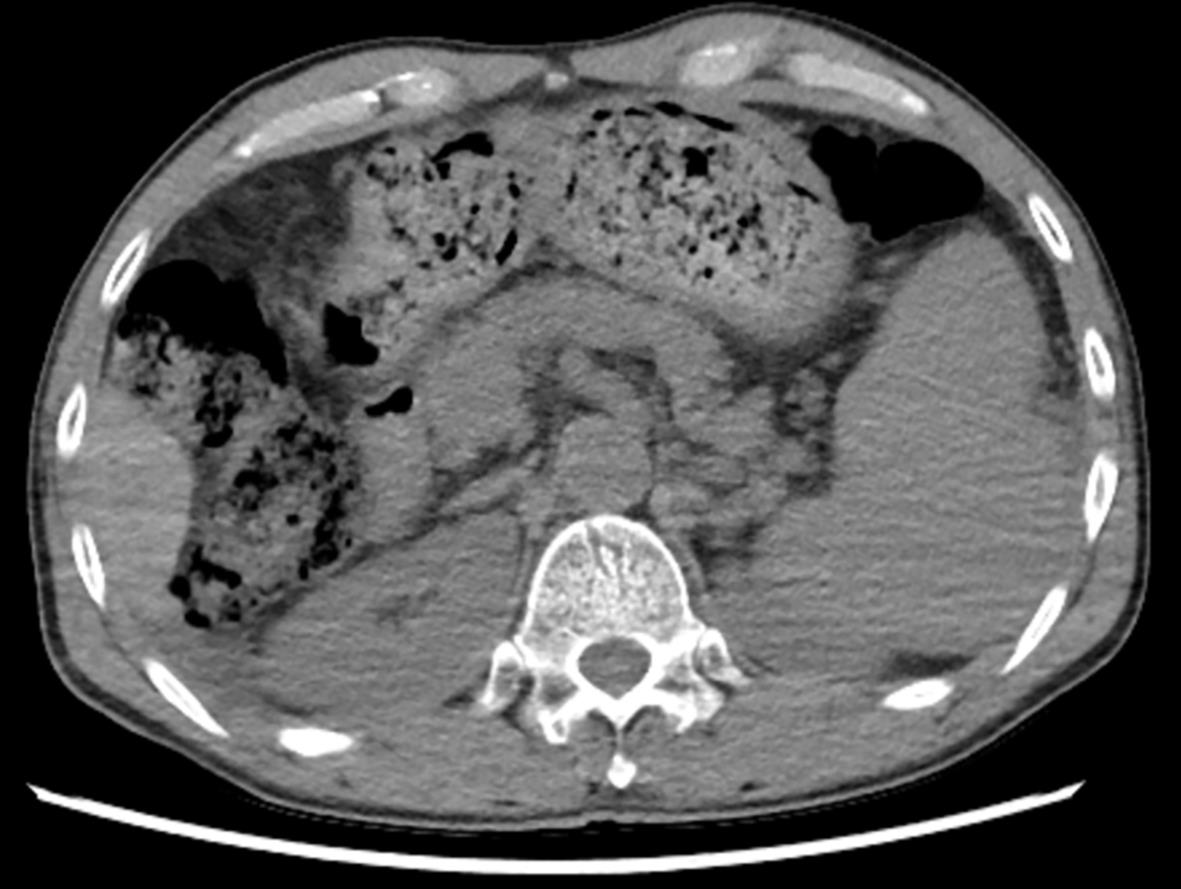

Pancreatic Disease

Efficacy and safety of omental wrapping technique for pancreaticojejunal anastomosis in preventing complications after pancreaticoduodenectomy: A Meta-analysis

Yabo SHI, Yang LI, Huabing LIU, Zhicong WANG, Changwen HUANG

2024, 40(1): 129-137. DOI: 10.12449/JCH240122

Abstract(1136) HTML (325) PDF (2134KB)(87)

Abstract:

Objective  To systematically evaluate the efficacy and safety of omental wrapping technique for pancreaticojejunal anastomosis in preventing complications after pancreaticoduodenectomy.  Methods  This study was conducted according to the PRISMA guideline. English and Chinese databases including CNKI, Wanfang Data, VIP, CBM, the Cochrane Library, PubMed, Embase, and Web of Science were searched for clinical studies on omental wrapping technique for pancreaticojejunal anastomosis in preventing complications after pancreaticoduodenectomy published up to November 2022, and Stata 16 and Review Manager 5.4 were used to perform the meta-analysis.  Results  A total of 15 studies with 1 830 patients were included in this study. The meta-analysis showed that the omental wrapping group had a significantly lower overall incidence rate of postoperative pancreatic fistula (POPF) than the non-omental wrapping group (odds ratio [OR]=0.30, 95% confidence interval [CI]: 0.22‍ ‍—‍ ‍0.41, P<0.001), and the subgroup analysis showed that the omental wrapping group had a significantly lower incidence rate of grade B/C POPF than the non-omental wrapping group (OR=0.29, 95%CI: 0.21‍ ‍—‍ ‍0.39, P<0.001). Compared with the non-omental wrapping group, the omental wrapping group had significantly lower incidence rates of postoperative bile leakage (OR=0.30, 95%CI: 0.16‍ ‍—‍ ‍0.56, P<0.001), postoperative hemorrhage (OR=0.35, 95%CI: 0.24‍ ‍—‍ ‍0.53, P<0.001), delayed gastric emptying (OR=0.45, 95%CI: 0.31‍ ‍—‍ ‍0.64, P<0.001), abdominal infection (OR=0.55, 95%CI: 0.40‍ ‍—‍ ‍0.75, P<0.001), reoperation (OR=0.31, 95%CI: 0.18‍ ‍—‍ ‍0.54, P<0.001), and death within 30 days after surgery (OR=0.42, 95%CI: 0.22‍ ‍—‍ ‍0.80, P=0.009), a significantly earlier time to diet (mean difference [MD]=-0.98, 95%CI: -1.84 to -0.11, P=0.03), and a significantly shorter length of postoperative hospital stay (MD=-2.44, 95%CI: -4.10 to -0.77, P=0.004). There were no significant differences between the two groups in the time of operation (MD=-13.68, 95%CI: -28.31 to -0.95, P=0.07) and intraoperative blood loss (MD=-17.26, 95%CI: -57.55 to -23.03, P=0.40).  Conclusion  Omental wrapping can reduce the incidence rates of postoperative complications such as pancreatic fistula, bile leakage, postoperative hemorrhage, abdominal infection, and delayed gastric emptying, improve the prognosis of patients, and shorten the length of hospital stay, without increasing surgical difficulty or time of operation.